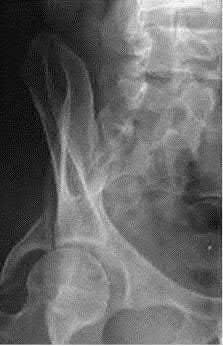

A 27 year-old patient sustains a fracture-dislocation of the acetabulum. Pelvic radiographs (Figures A and B) are taken at initial presentation and a CT scan (Figures C and D) is performed after reduction of the hip in the emergency room. What is the importance of the finding highlighted in the CT scan cuts?

The CT images shown in Figures C and D display significant marginal impaction of the joint surface.

Marginal impaction is common in posterior wall fractures and fracture-dislocations. Critical review of CT imaging of posterior wall fractures can help with preoperative planning for identifying impaction of the articular surface of the acetabulum. Restoration of the sphericity of the acetabulum to match that of the femoral head is important for successful outcome following ORIF of posterior wall fractures. A common surgical technique to accomplish joint surface restoration includes freeing the impacted articular segments, bone grafting of the void created to support the articular segments, and buttress plating of the posterior wall fracture fragments.

Figures A and B are radiographs of the posterior wall fracture and hip dislocation. They do not show the large amount of marginal impaction of the acetabular surface. Figure C (coronal reconstruction) and Figure D (sagittal reconstruction) point out a large a amount of marginal impaction of the acetabular. Note the disruption of the joint surface on the intact portion of the acetabulum.